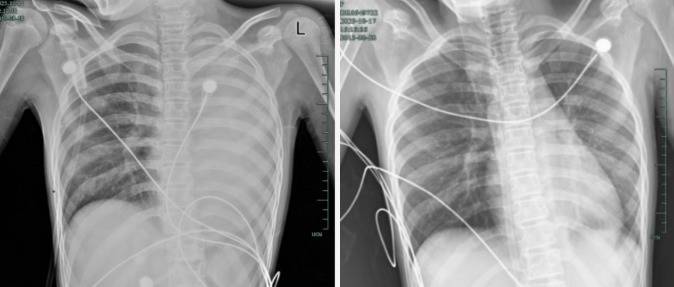

治疗前,左肺呈“白肺”状态;治疗后,“白肺”被吸收,心脏边缘清晰可见

入院后,她很快出现呼吸急促、胸闷胸痛,体温38.5℃,只能靠 5L/min 的面罩吸氧维持血氧,胸片显示左肺已完全呈 “白肺” 改变,肺部炎症进展迅猛。